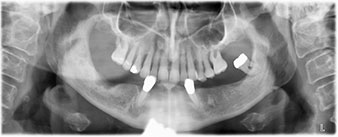

A three-dimensional cone beam computed tomography scan (CBCT, Planmeca) was performed to aid planning and minimize risks. This revealed that the quality and quantity of the available bone were sufficient for the surgery and immediate restoration using the Fast & Fixed method. Following the protocol for this concept, the implants are inserted at 35, 32, 42 and 45. Angling the distal implants by up to 45° shifts the emergence profile to posterior and generates a larger support polygon (Fig. 3).

Following the time required for the osseointegration, the final impression of the implants could be performed and the final denture produced accordingly (Fig. 19 and 20). At this point, the dentist and patient were able to decide together whether to use a ceramic or acrylic veneer and a zirconium or metal framework. In this case, Dr. Pascu’s team decided on an acrylic veneer based on the unclear prognosis for the maxillary dentition and the fact that tooth 24 is elongated. This type of veneer is generally considerably easier to adapt and can thus be subsequently altered to reflect the new situation in the maxilla.

Osseointegration

Fig. 19

Implants

Fig. 20